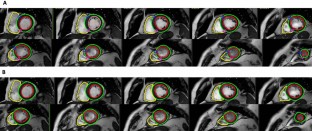

Fig. 1